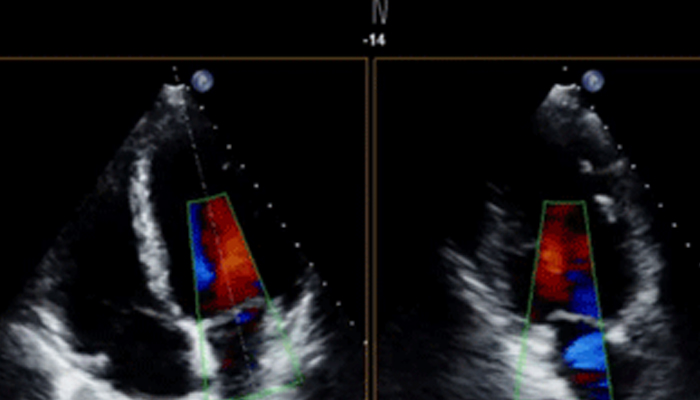

تشهد حاليًا خيارات العلاج التي لا تتطلب سوى تدخل جراحي محدود في القلب والأوعية الدموية انتشارًا ملحوظًا. ولقد ساهمت التطورات الأخيرة في مجالات التشخيص والتوجيه بالصور المباشرة Live Image Guidance والمعلوماتية في جعل هذا الأمر ممكنًا. بالتعاون مع أشهر أطباء أمراض القلب، ابتكرنا حلولاً تساهم في منح المرضى الفرصة لتغيير حياتهم. فهذه الحلول تساعد في تسريع سير العمل وزيادة فعالية الطاقم الطبي وتوفير أفكار سريرية.